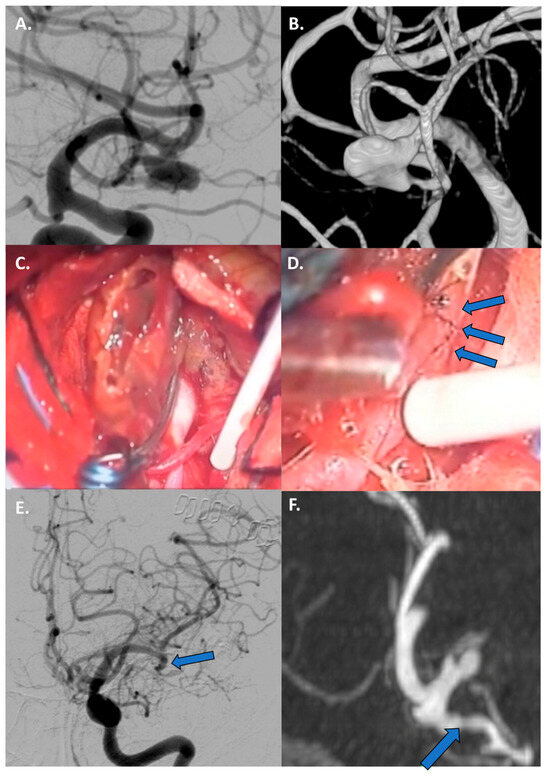

4.3.1. Large/Giant Aneurysm Size and Fusiform Shape

4.3.2. Vessels Branching from the Dome

4.3.3. Thrombosed Aneurysm and/or Previously Treated Aneurysms